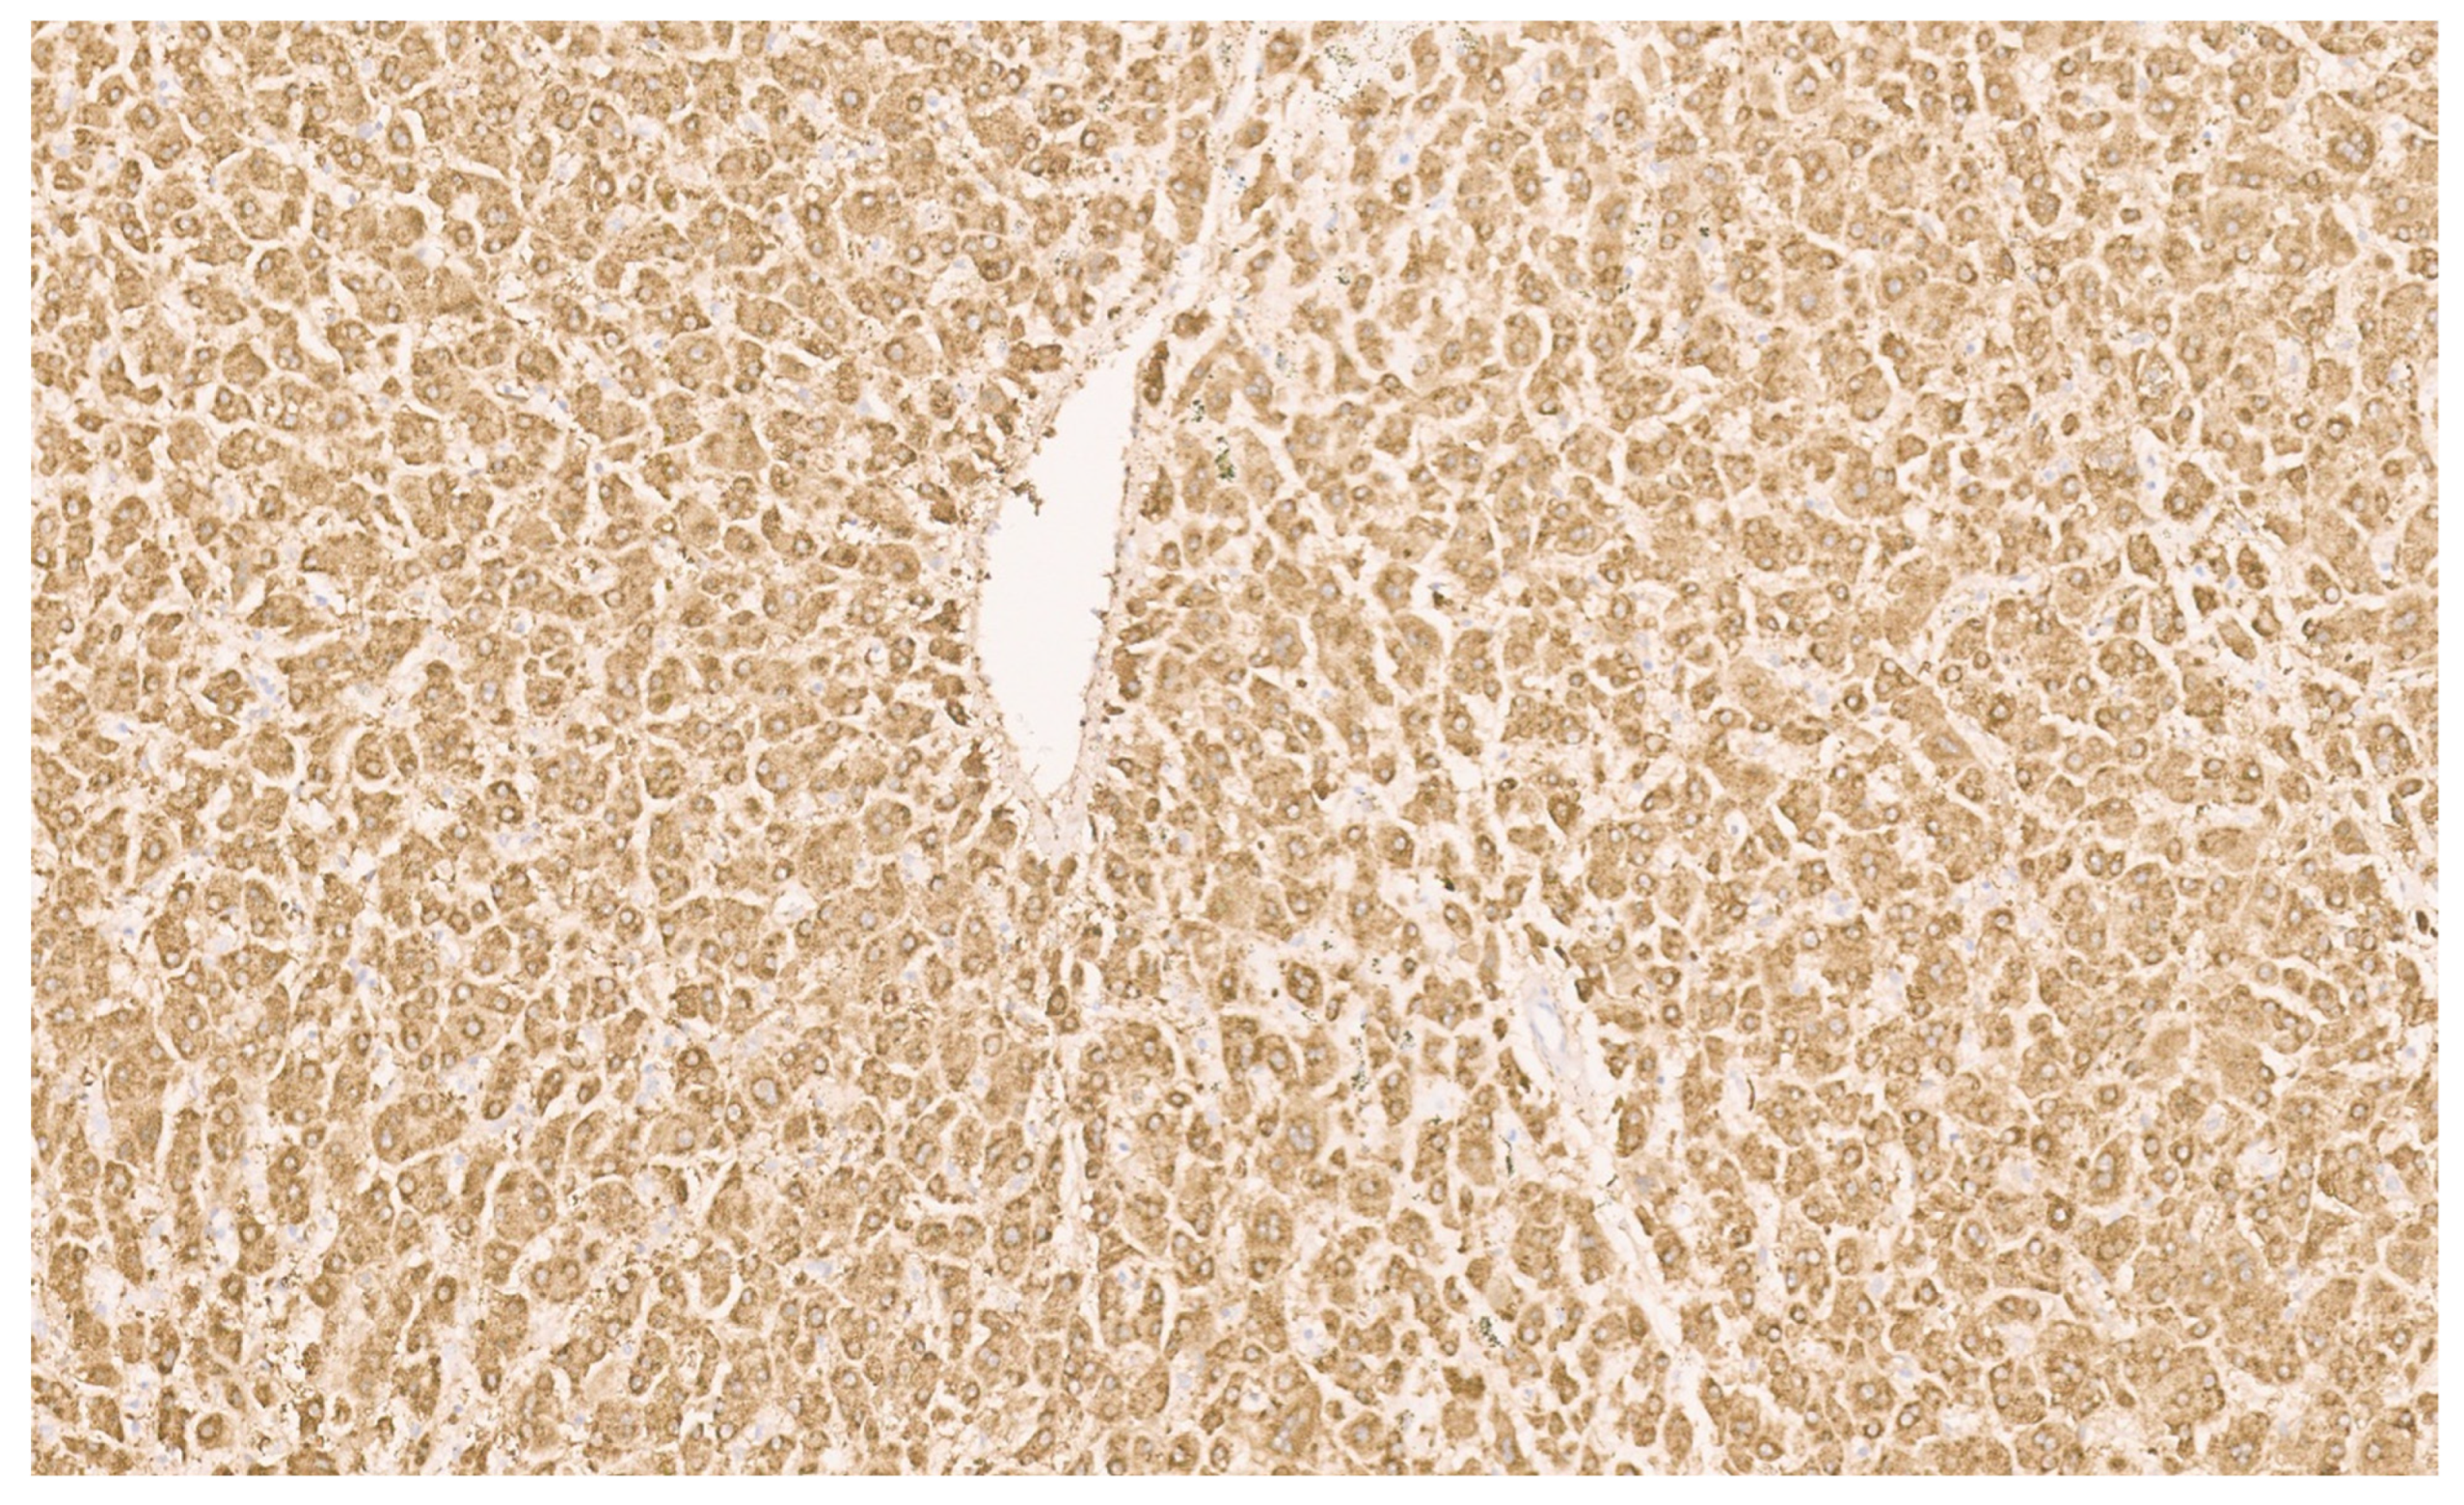

16.3. Pathology

| Histopathology | Well Differentiated | Moderately Differentiated | Poorly Differentiated |

|---|---|---|---|

| Arrangement | Trabeculae that are at least 3 cells thick and lined by sinusoids, pseudoacinar arrangement | Trabeculae that are 15–20 cells thick lined by sinusoids, pseudoacinar arrangement | Sheets or nests of cells not resembling hepatocytes. |

| Cells and nuclei | Resemble hepatocytes with mild nuclear pleomorphism, centrally placed round nuclei, and abundant cytoplasm | Moderate nuclear pleomorphism, large nuclei with prominent nucleoli and intranuclear inclusions, abundant cytoplasm. | High N/C ratio, nuclear pleomorphism, prominent nucleoli and intranuclear inclusions, numerous mitosis |

| Necrosis | Usually absent | May be seen | Present |

| Immunohistochemistry | Variable glypican 3 and glutamine synthetase levels. Negative for β-catenin nuclear staining | Glypican 3 and glutamine synthetase are positive in 50% of cases, β-catenin is variable | Glypican 3 and glutamine synthetase |